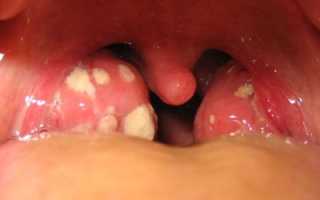

Проявления хронического тонзиллита:

- покраснение краев небных дужек;

- разрыхление и уплотнение миндалины;

- наличие гнойных пробок;